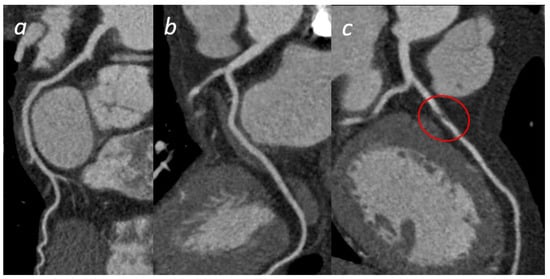

Figure 2.

A 28 y/o man presented at the emergency department with fever and chest pain. At the admission, cardiac enzymes were elevated and ECG did not show any alteration. Cardiac MRI was performed 1 day later and revealed pericardial alteration: presence of edema (a) and post-inflammatory fibrosis (b,c).